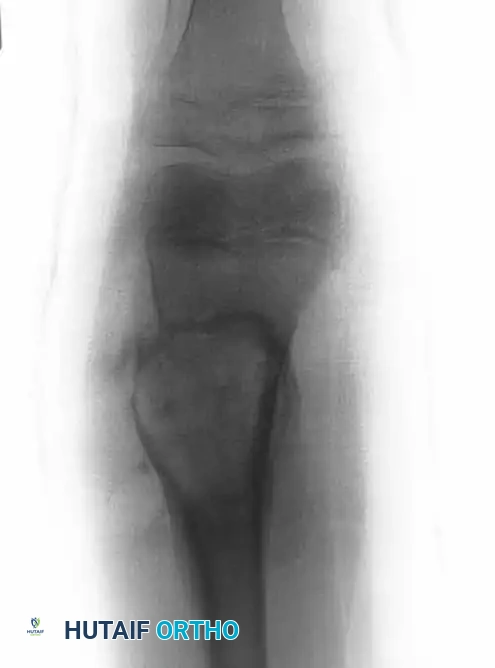

Intraoperative Imaging and Margin Assessment

Continuous intraoperative assessment using fluoroscopy and frozen section pathology is mandatory. The following images demonstrate various stages of complex upper extremity resections, allograft preparations, and prosthetic implantations across the humerus and elbow joint.

Distal Humerus and Elbow Reconstruction

When tumors involve the distal humerus, resection often requires sacrifice of the collateral ligaments and the articular surface of the elbow. Reconstruction is typically achieved using a linked, semi-constrained total elbow arthroplasty designed for oncologic defects.